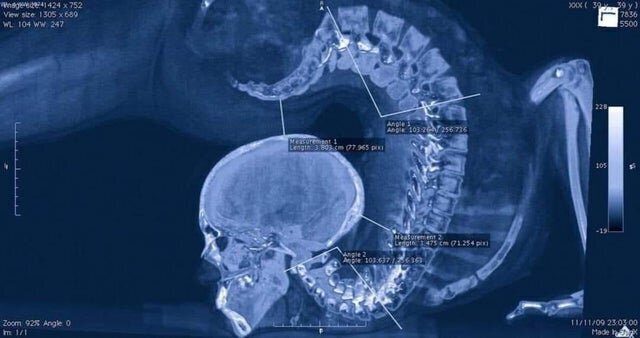

Обратите внимание на позвоночник: рентген гимнастки в прогибе

Рентген гимнастки — готовый персонаж для фильма «Человек-скорпион»

Мне вообще что-то инопланетное померещилось